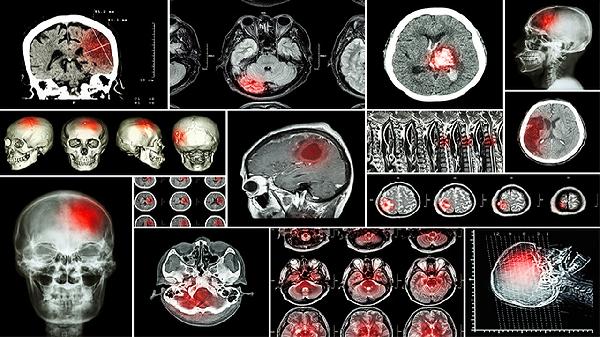

日常可练习“鸣天鼓”按摩法:双手掌心压耳,食指叠中指弹击玉枕穴36次,能醒脑开窍。饮食宜多食核桃、黑芝麻等补肾益髓之物,避免长时间低头耗伤督脉阳气。太极拳“云手”动作能有效锻炼小脑-前庭联动功能,建议每周练习3次以上。若出现持续头晕、步态异常等症状,应及时进行头颅MRI检查排除器质性病变。